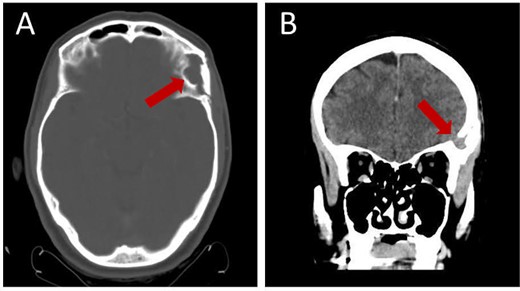

Prior diagnostic imaging included a computed tomography (CT) scan, revealing a hypodense lesion in the left fronto-zygomatic region (Fig. 1). Subsequent brain magnetic resonance imaging (MRI) showed a high-intensity lesion on T1-weighted images (T1WI) (Fig. 2A), and an iso-to-hyperintense lesion on T2-weighted images (T2WI) (Fig. 2B).

Pre-operative axial CT scan displaying a well-defined, low attenuating lesion in the left fronto-zygomatic region.

Follow-up brain CT, 3 months post-operation, showing complete resection of the lesion without residual tissue: (A) axial view and (B) coronal view.